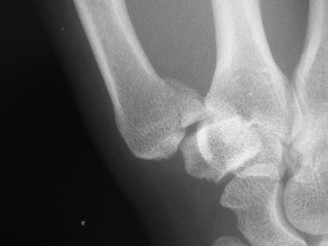

CASE 25 A 42-year-old man presents to the hospital with pain and swelling of th…